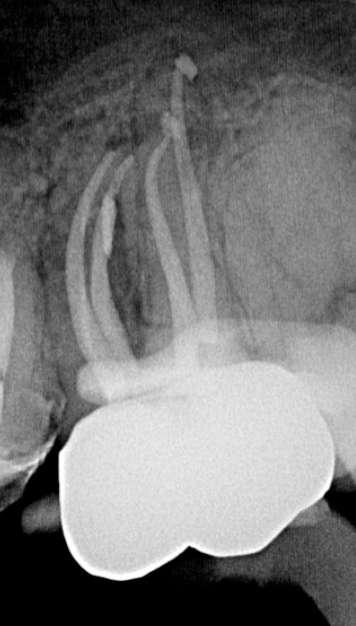

Präoperativ

Der erste untere, linke Backenzahn zeigt einen Zerfall auf dem distalen Teil mit dem Symptom einer irreversiblen Pulpitis. Zuerst wird der Karies entfernt und der Zahn wird mit einer temporären Füllung wieder aufgebaut. Danach wird der Kofferdam platziert und der Zugangshohlraum steht.

Vier Kanäle wurden mit dem SX EdgeTaper Platinum eröffnet. Auch der koronale Teil wurde mit dem S1 EdgeTaper Platinum erweitert. Arbeitslänge und Durchgängigkeit werden mit einer #10 K-Feile erreicht. Die A #15 K-Feile wurde verwendet, um Länge und Durchgängigkeit zu gewährleisten. Dank der Technologie von EdgeNedo war ich im Stande, die Feile für eine komfortable Formgebung vorzuformen, auch wenn die Öffnung reduziert wurde. S1, S2, F1 und F2 EdgeEndo Platin wurde bis zur gesamten Länge des Kanals eingebracht.

Während der Isthmus-Reinigung zeigte sich zwischen den mesialen Kanälen ein zusätzlicher Kanal. Die Formgebungsphase erfolgte schnell und effizient dank SX zum F2.

Das Röntgenbild zeigte eine große Länge und einen gemeinsamen Ausgang für zwei der drei mesialen Kanäle.

Die Wurzelfüllung erfolgte mit einer einzigen Kegeltechnik unter Verwendung des BUSA EndoSequence Bioceramic Sealer. Das Post-OP-Röntgen zeigt sehr hohe Dichte in der gesamten Länge der Wurzelfüllung.